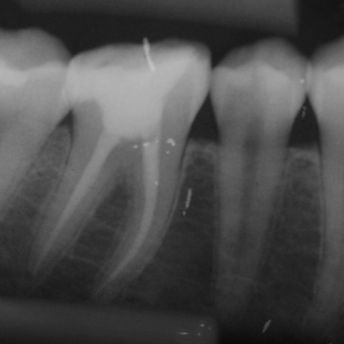

TRATAMENTO E RETRATAMENTO ENDODÔNTICO

DESOBTURAÇÃO

Câmera Intraoral;

Rx portatil;

Sensor rx;